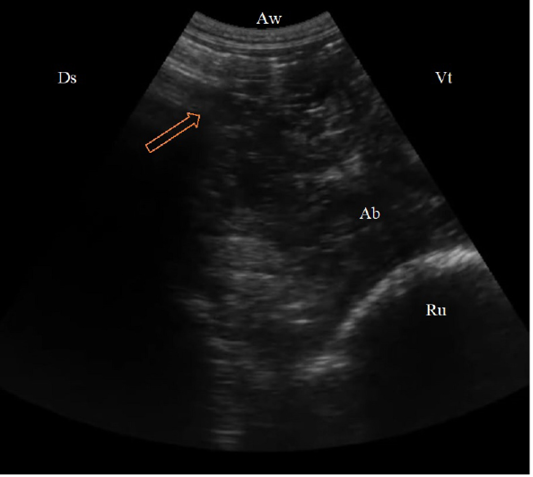

(B. Mode ultrasonographic image in a cow with left abomasal displacement. The abomasum displaced to the left side between the rumen (Ru) and the left abdominal wall as imaged from the left 11th ICS, the reverberation artifacts of the gas cap (arrow) appeared dorsally, followed by the hypoechoic abomasal contents (Ab), Aw: Abdominal wall, Ds: Dorsal, Vt: Ventral.)